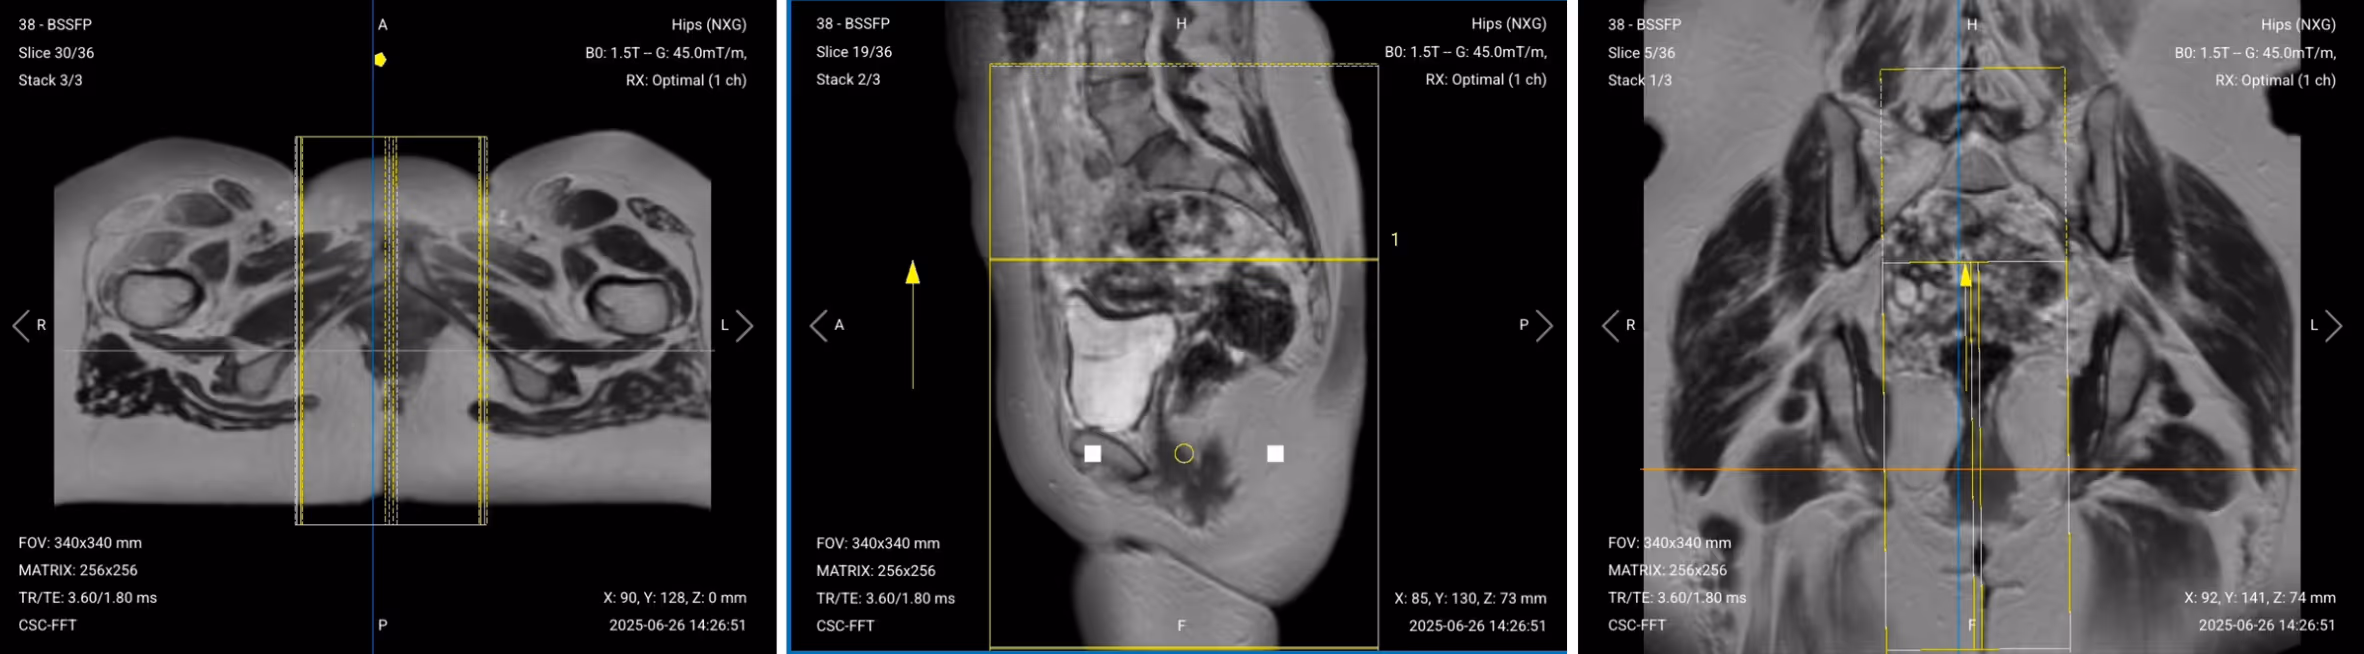

We then acquire axial views perpendicular to the anal canal for the most diagnostic images, as they show tracts crossing from internal to external sphincter clearly.

✅ Axial T2 STIR of Anal Canal – Correct Image Example:

Things to Look for in Axial T2 Fat-Saturated:

✅ Coronal T2 STIR of Anal Canal – Correct Image Example:

Things to Look for in Coronal T2 Fat-Saturated: